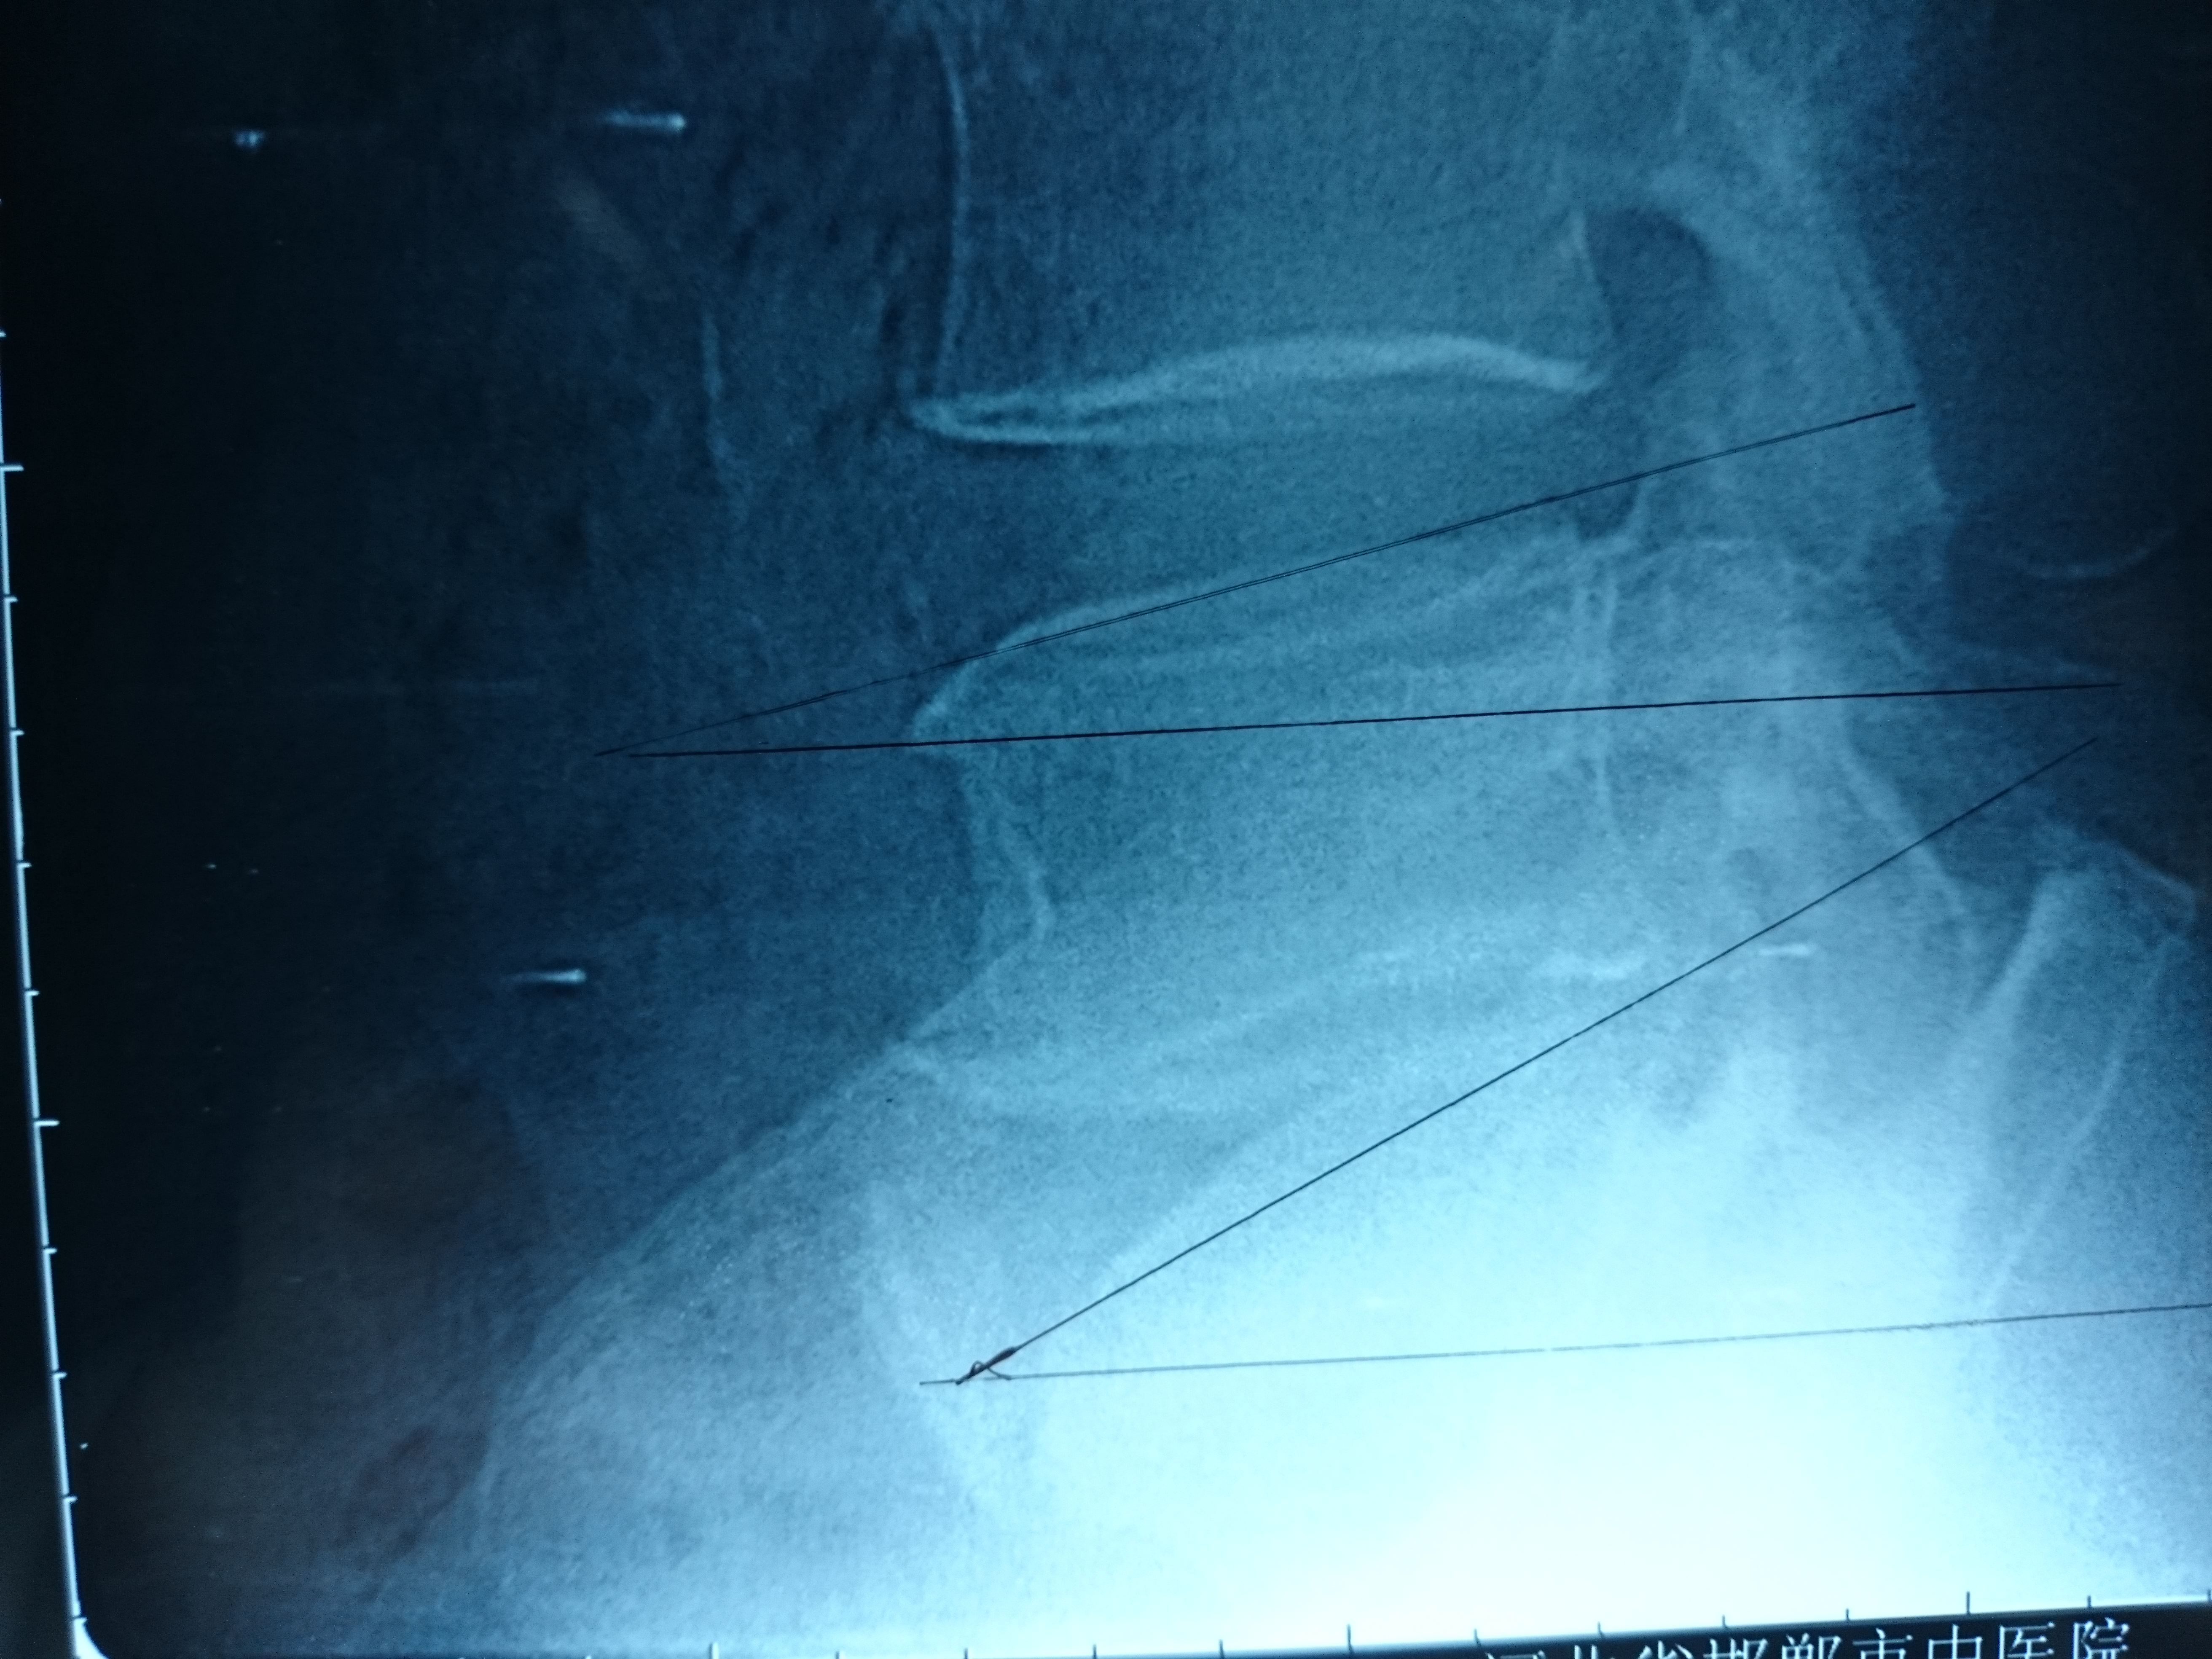

首页 > 张恒云工作室 > 影像资料 三十四